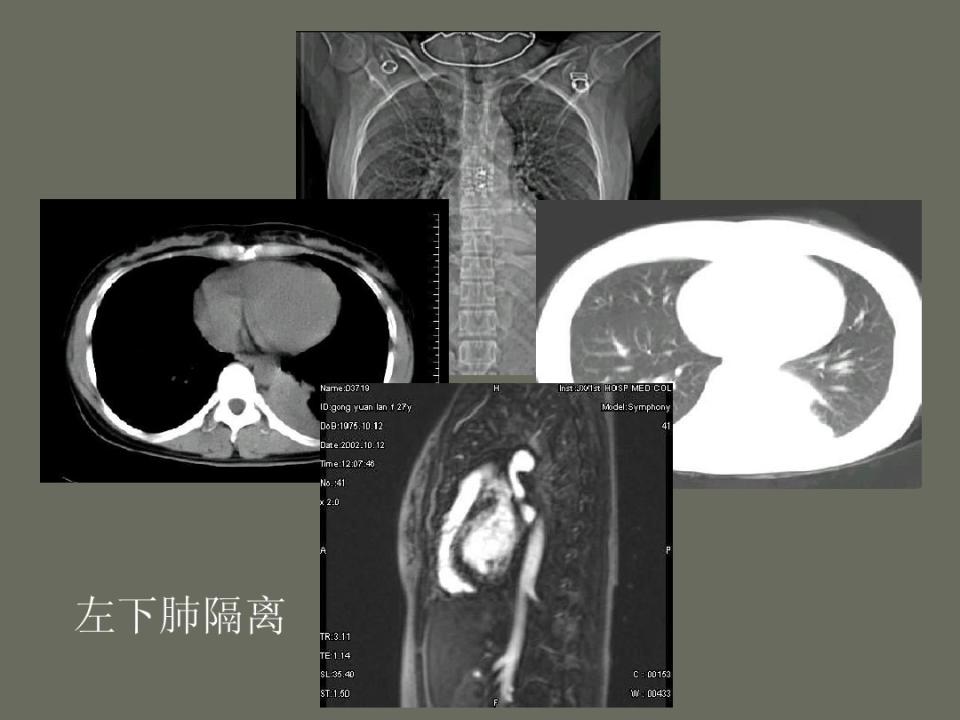

肺部先天性疾病的影像诊断